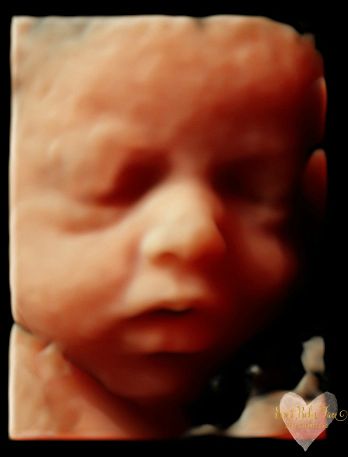

3D/4D/5D Ultrasound Gallery

Take a peek at our Photo Gallery. All of our 2D, 3D, 4D, HD elective ultrasound images are truly ours. They come directly off our machine from our highly trained staff. We can start getting great 3D/4D images as early as 10 weeks!